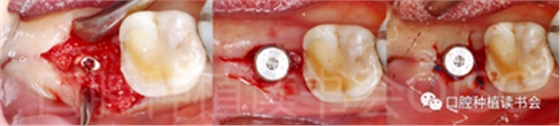

5.3.9 術(shù)后第6周,47行種植2期手術(shù),可見種植體周圍愈合良好,牙齦成型后,旋入愈合基臺(tái)(圖22)。

圖22 種植體周圍獲得了良好的骨整合。